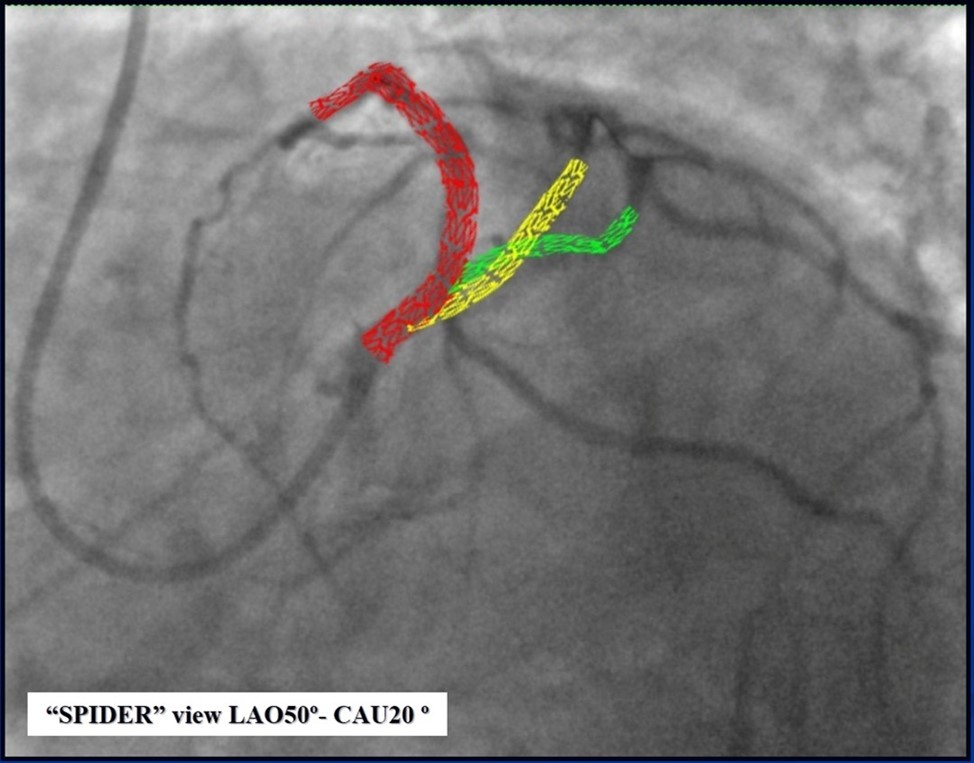

Figure 12.Schematic presentation of the implanted stents, “spider” projection.

Schematic presentation of the implanted stents, “spider” projection.